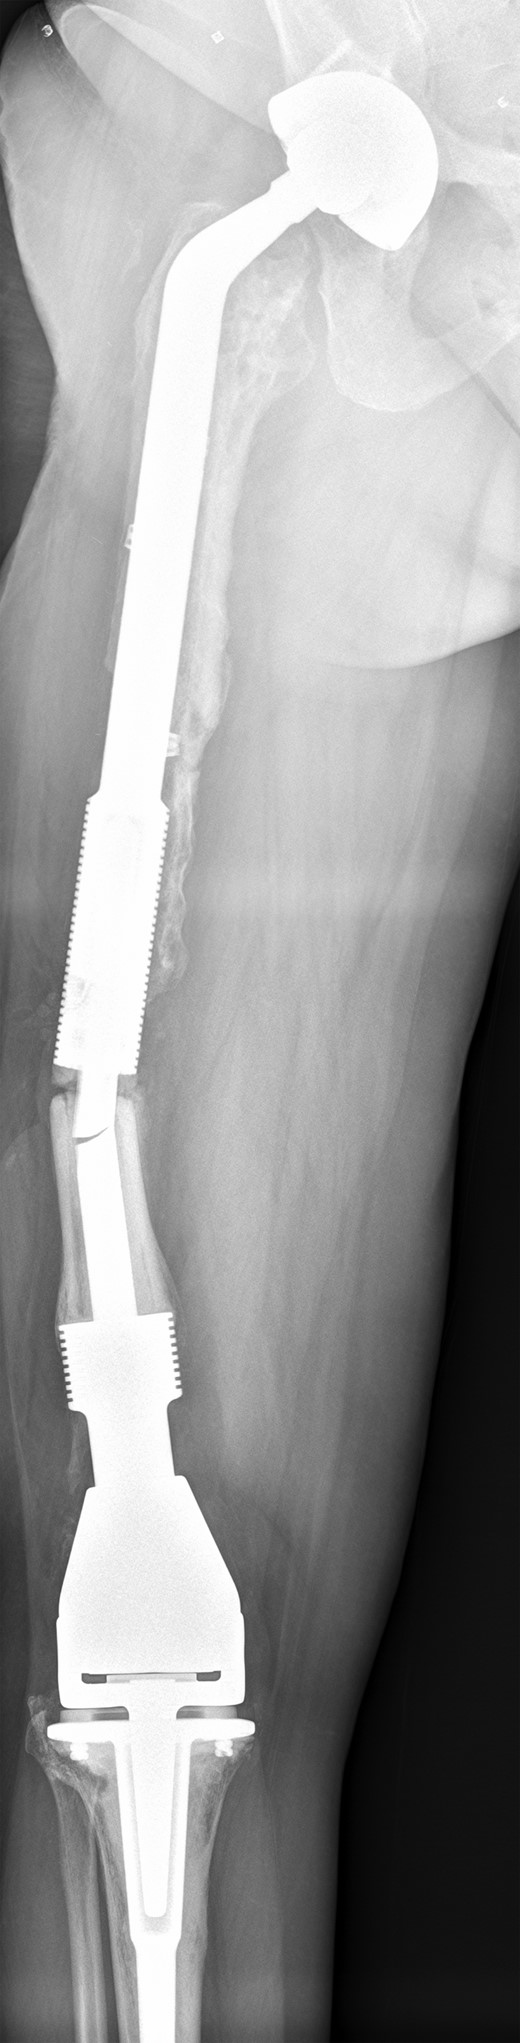

The operation was carried out by the senior author and the customized distal femoral prosthesis was successfully cemented over the pre-existing internal proximal femoral replacement (Figs 6 and 7).

Retained proximal femoral component with new custom-made cement-linked distal femoral prosthesis visible in lower half of the image.

New custom-made distal femoral prosthesis cement-linked to original salvage proximal femoral component visible in upper half of the image.